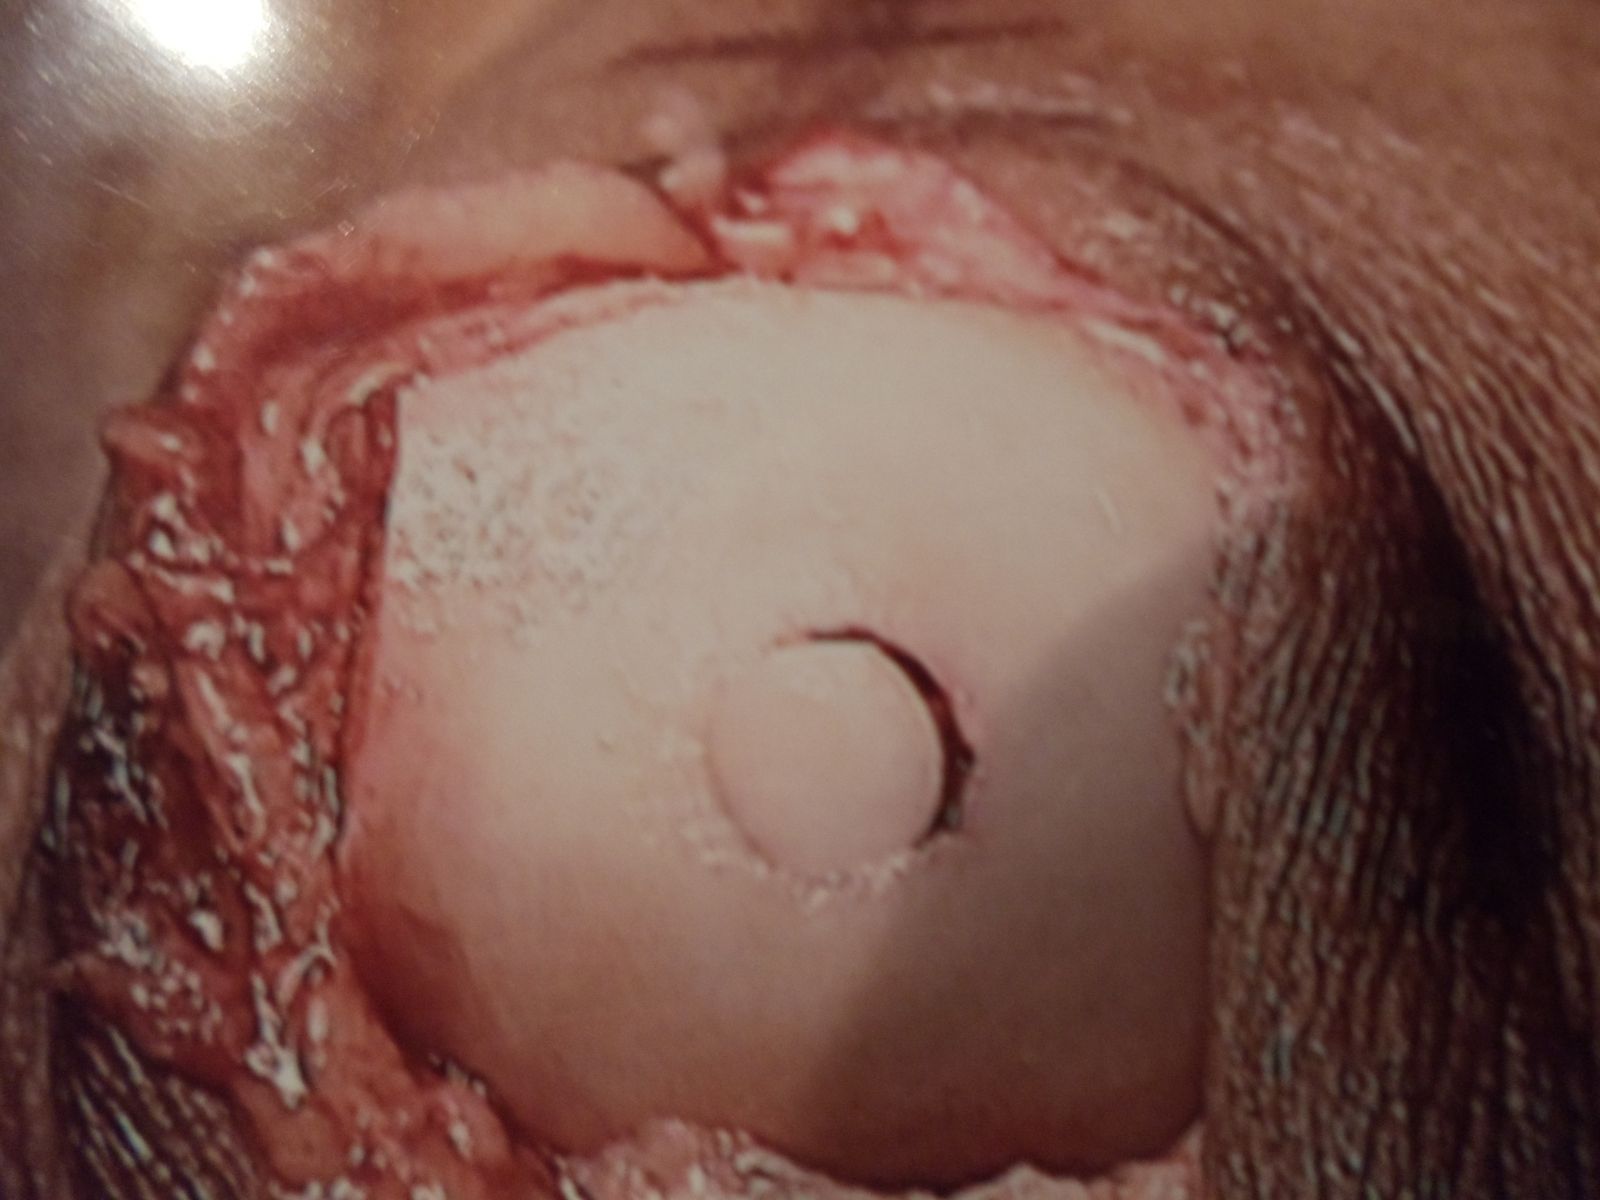

Osteochondral Autograft Transfer System (O.A.T.S.)

Series of Pics of Microfracture of large OCD of the Talar Dome